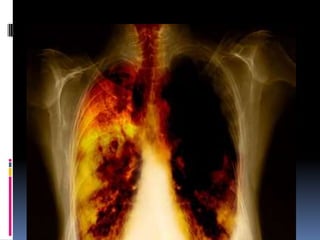

The lungs are made up of approximately 350 million tiny sacs called alveoli, where carbon dioxide from the body is exchanged for oxygen from the air. Various diseases that affect the lungs either destroy the alveoli directly, as does emphysema, or impair the alveoli’s ability to exchange gases. This picture shows the effects of emphysema (caused by smoking) on lung tissue.